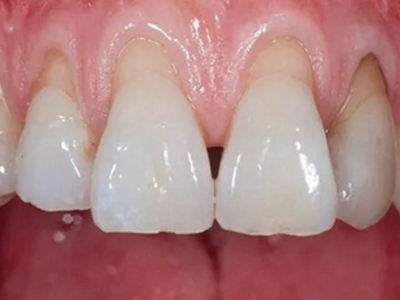

牙龈退缩牙龈萎缩露出牙根图

牙龈退缩发作于上排尖牙和磨牙处,导致牙根暴露在外,伴有牙齿松动、口臭、牙根面敏感等症状,是由于刷牙不当、牙周炎等因素引起。